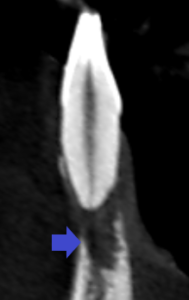

冠状断のCT画像の赤い矢印の歯の歯列矯正治療後の矢状断のCT画像です。

矢印の先の根の先は平らに歯根吸収し、更に歯槽骨から外に飛び出していました。